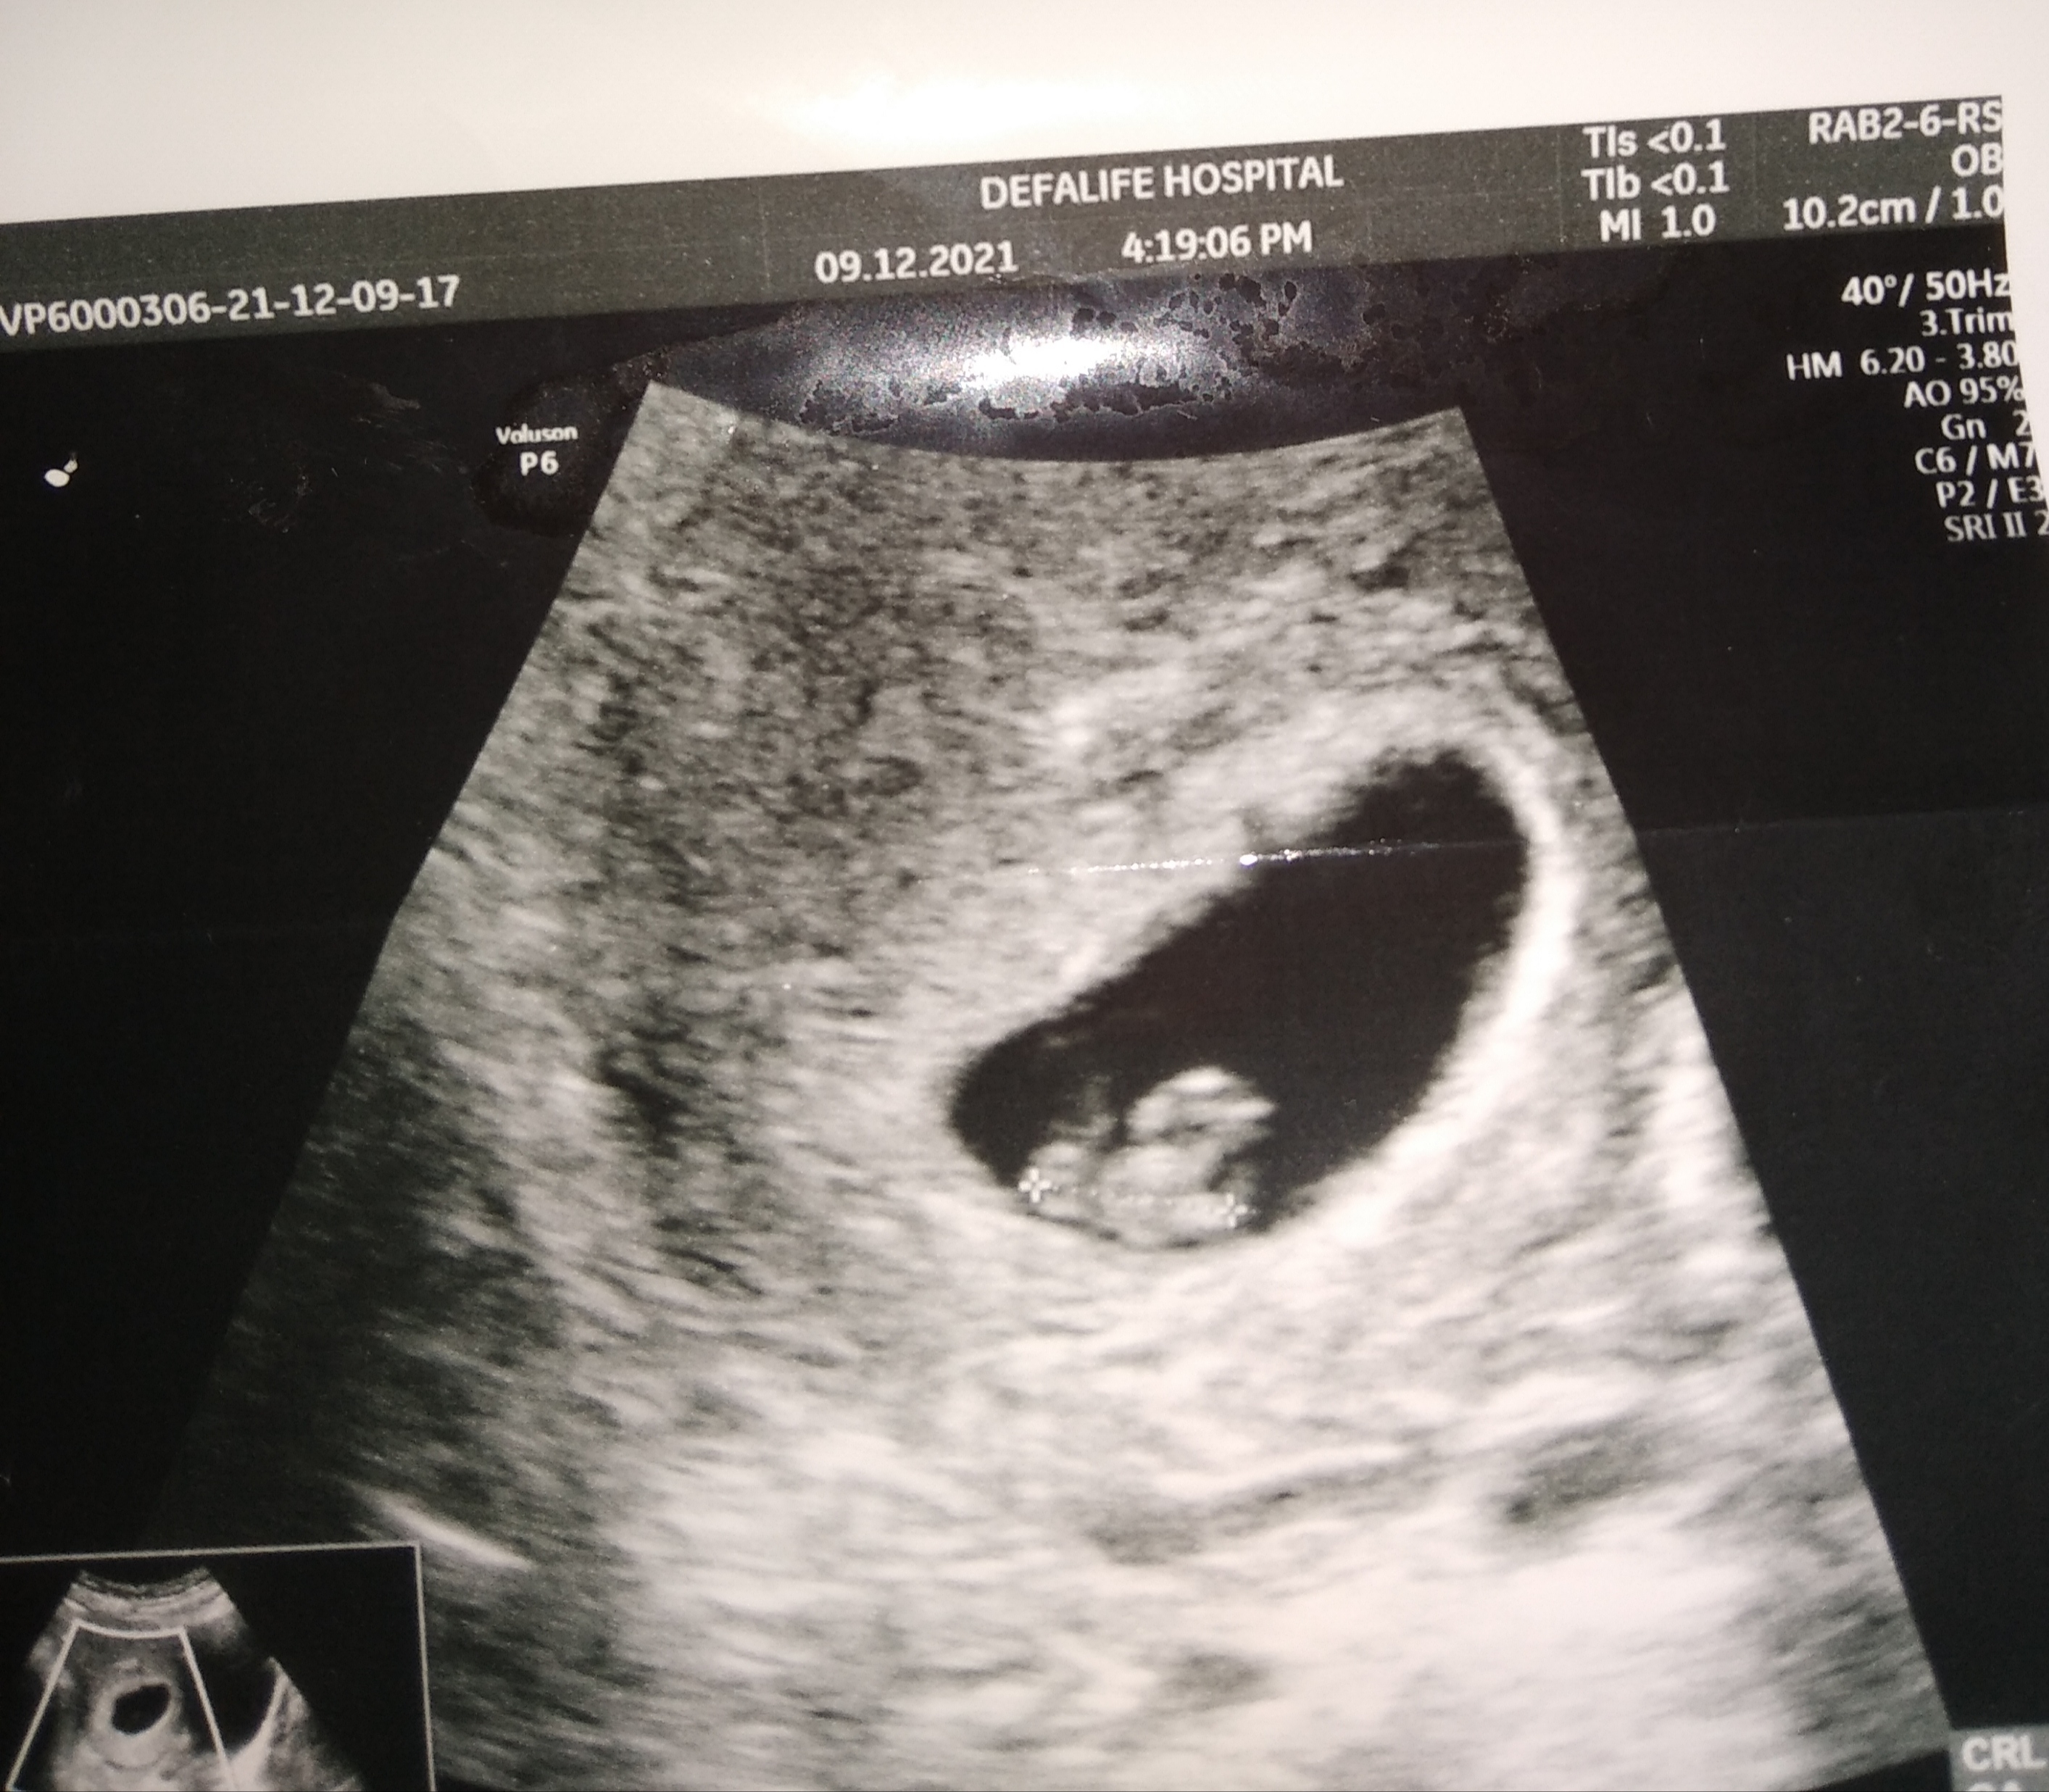

Ben pek bir şey goremedim başka daha net bir görsel var mı?